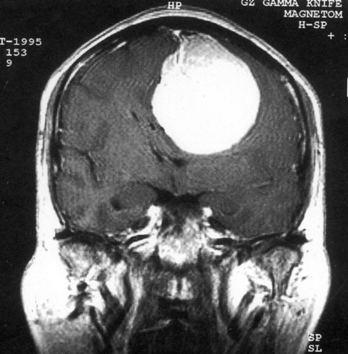

问题 病历摘要:??患者女性,37岁。大便时突起炸裂样头痛3小时,伴喷射样呕吐。既往体健。体检:T37.5℃,BP145/90mmHg,R20次/分,P85次/分。神志清楚,颅神经检查无异常,颈强直,克、布氏征(-),四肢肌力、肌张力正常,病理征(-)。 根据病史,最可能的诊断是什么?

选项 A.脑栓塞 B.脑血栓形成 C.蛛网膜下腔出血 D.脑炎 E.血管性头痛 F.脑膜炎 G.脑出血

答案 C